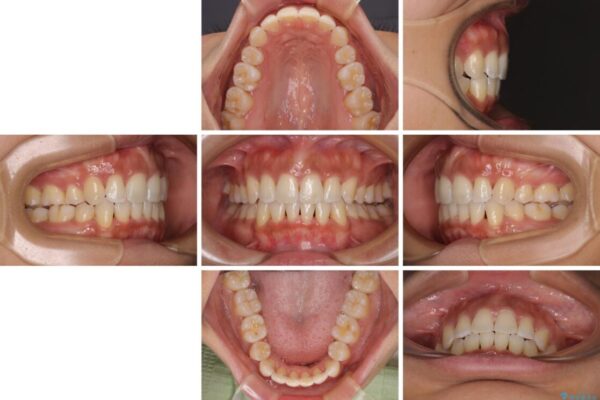

治療前

• 抜歯矯正で唇を閉じやすく 目立たないワイヤー装置 治療前画像